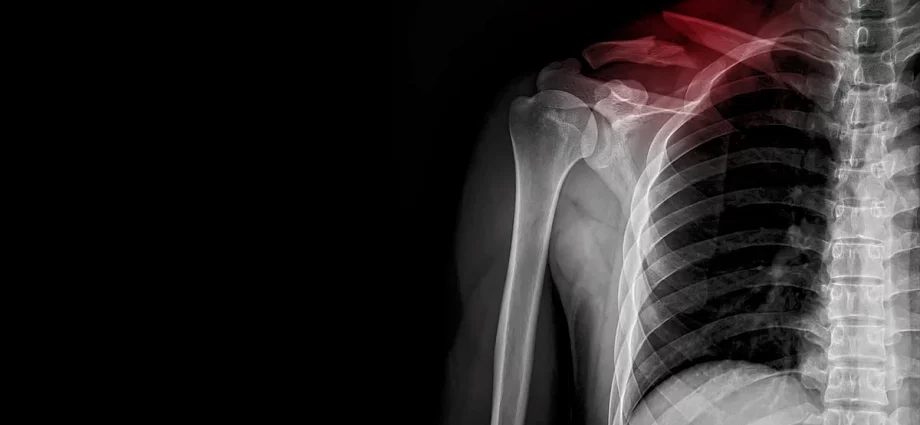

WEDNESDAY, July 9, 2025 (HealthDay News) — More kids are being hospitalized for broken collarbones, a new study has found.

In fact, the hospitalization rate for broken collarbones more than doubled among children between 2014 and 2021, researchers reported.

The hospitalization rate for broken collarbones rose to a high of 2.6% in 2021 from a low of 0.8% in 2014, researchers report.